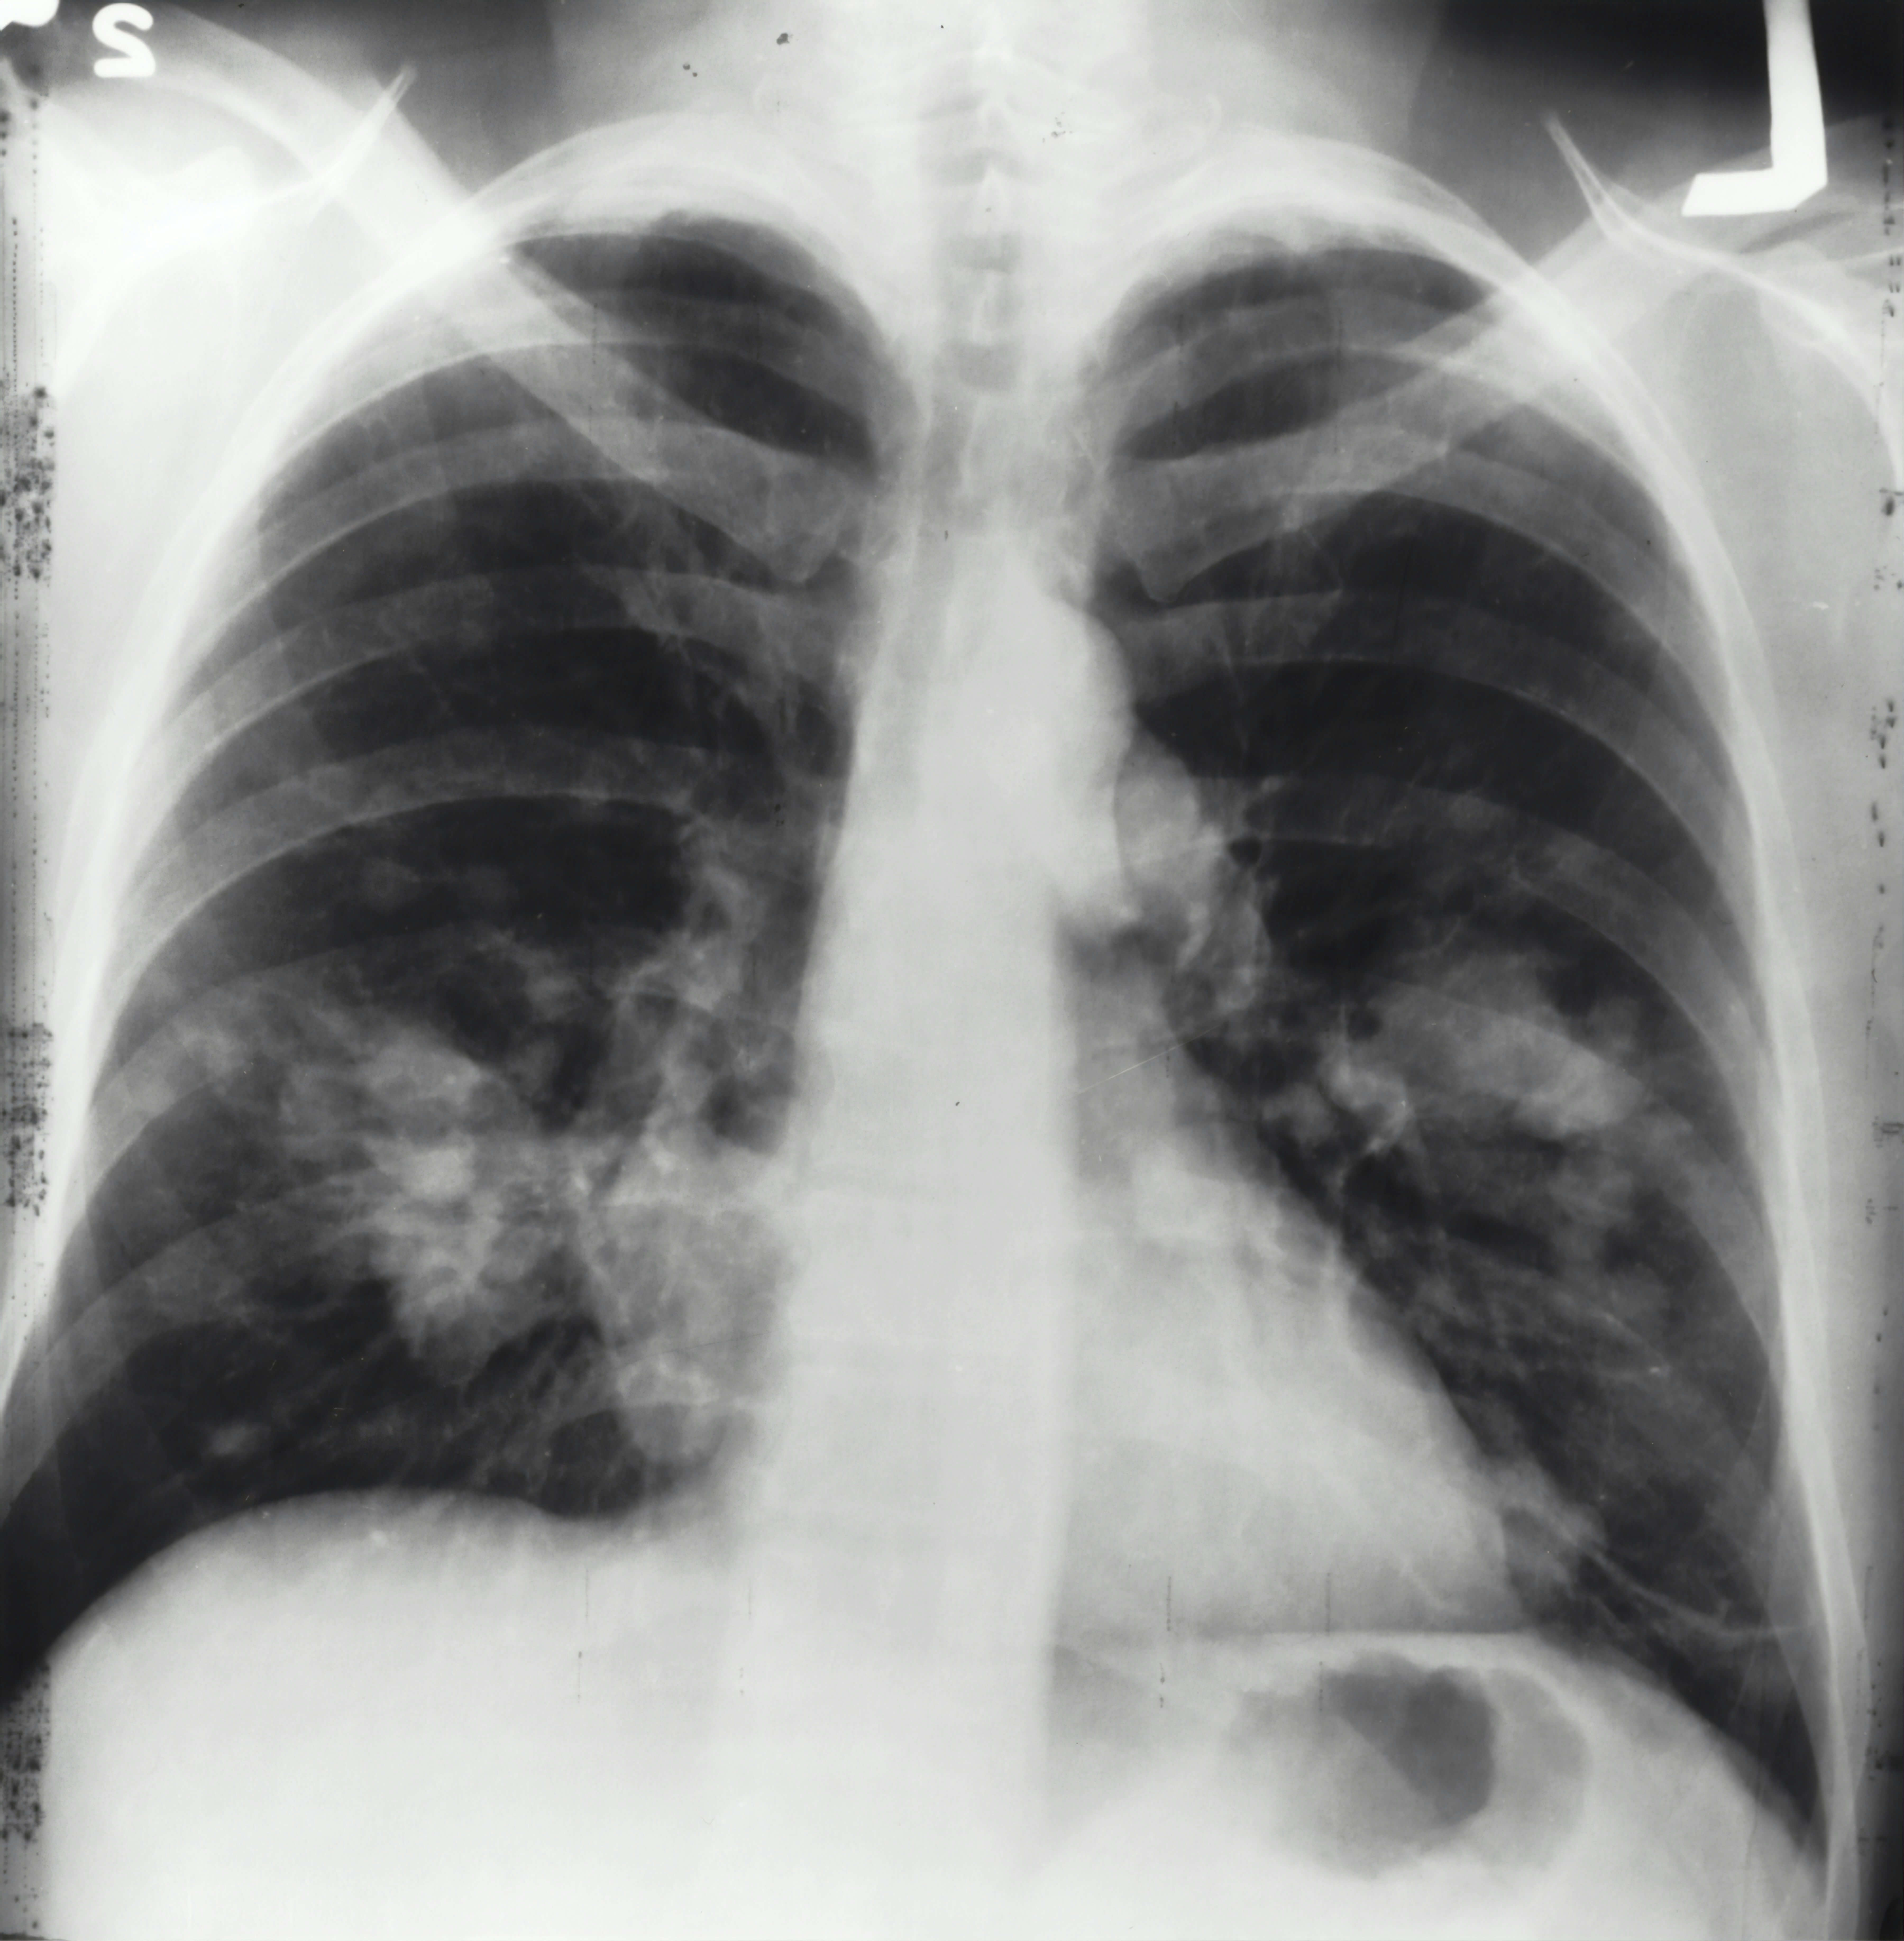

현대 사회에서 폐암은 조기 발견이 매우 어려운 질환으로 알려져 있습니다.

초기에는 특별한 증상이 거의 나타나지 않아 대부분 병이 상당히 진행된 후에야 이상을 느끼고 병원을 찾게 됩니다.

특히 흡연자나 간접흡연에 자주 노출되는 분들, 그리고 대기 오염이 심한 환경에서 생활하는 분들은 폐암 초기증상에 더욱 민감하게 주의를 기울일 필요가 있습니다.

폐암은 초기에 발견될 경우 5년 생존율이 50% 이상으로 높아지지만, 진행된 상태에서 발견되면 생존율이 크게 떨어집니다.

폐암, 왜 조기발견이 중요할까요?

따라서 폐암 초기증상을 알고 조기에 발견하는 것이 생명을 지키는 첫 번째 단계입니다.

폐암은 초기에는 특별한 증상이 나타나지 않는 경우가 많지만, 몸에서 보내는 미세한 신호들이 있습니다.